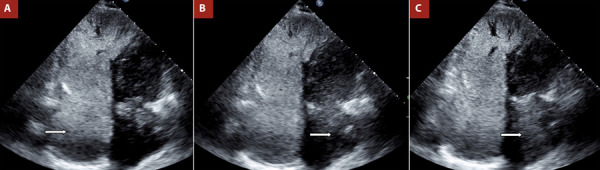

肺动脉高压的诊断方法采用心脏成像,特别是超声心动图,提供了一个实用的,容易获得的,高度有价值的工具。它有助于建立初步诊断的可能性,提供预后信息,并支持病原学评估。搅动生理盐水对比试验,也被称为气泡对比超声心动图,不仅可以帮助确诊,而且可以描述病情并确定肺动脉高压的各种潜在原因。

The diagnostic approach to pulmonary hypertension using cardiac imaging, particularly echocardiography, provides a practical, accessible, and highly valuable tool. It helps establish the initial diagnostic probability, offers prognostic information, and supports aetiological assessment. The agitated saline contrast test, also referred to as bubble contrast echocardiography, can aid not only in confirming the diagnosis but also in characterising the condition and identifying various underlying causes of pulmonary hypertension.